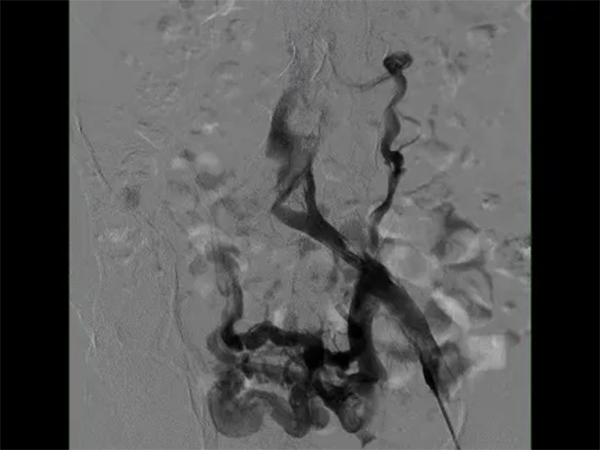

在與患者及家屬進(jìn)行了詳細(xì)的交流后,患者決定住院治療。在經(jīng)過了詳細(xì)的病情分析后,介入科肖晉昌團(tuán)隊(duì)為其制定了“髂靜脈造影+球囊擴(kuò)張+支架置入”的治療計(jì)劃。術(shù)中造影發(fā)現(xiàn)患者左髂總靜脈近心端重度狹窄,周圍側(cè)支開放,狹窄兩端壓差明顯,均提示患者存在重度的髂靜脈壓迫(圖3)。予以球囊擴(kuò)張狹窄處(圖4),然后行支架置入(圖5)。支架置入后造影患者左髂靜脈血液回流明顯改善,周圍側(cè)支減少。術(shù)后由張科醫(yī)師負(fù)責(zé)對(duì)其隨訪,經(jīng)過1個(gè)月的隨訪,患者目前下肢潰瘍基本愈合(圖6)。

圖3左髂靜脈造影